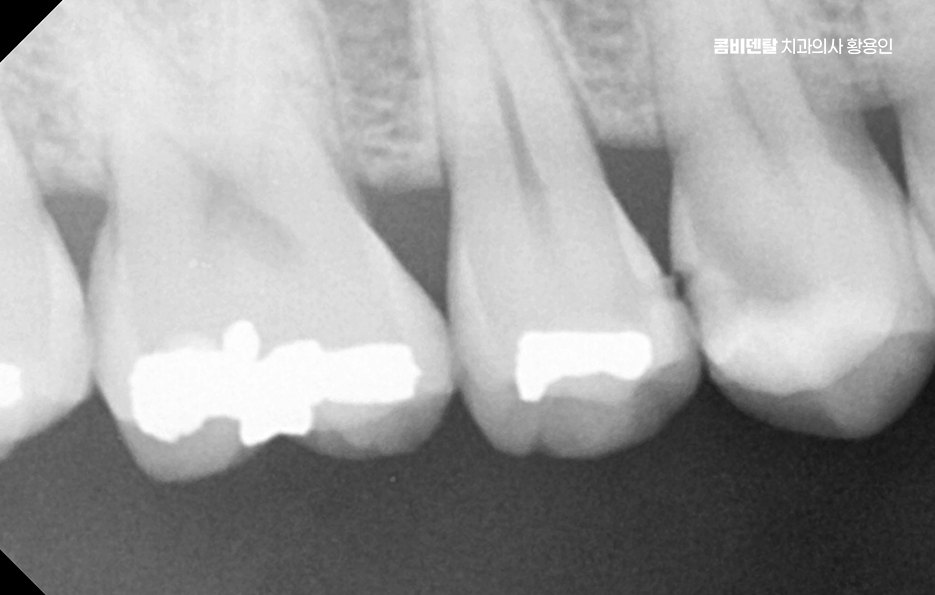

처음엔 안 보일 정도의 크랙이 생기고, 그 사이로 음식물과 세균이 침투하면서 2차 충치가 생기기 쉬운 것이며 특히 어금니처럼 씹는 힘이 센 부위에 들어간 아말감은 이런 팽창으로 인해 치아에 미세한 금을 만들고, 결국은 깨지거나 뿌리까지 손상이 가는 일이 생길 수 있기 때문에 늦지 않게 아말감 교체 레진 같은 재료로 재치료를 고려해야 할 수 있었어요

다음으로 아말감은 경계 부식이 문제가 될 수 있는데 접착력이 비교적 약한 편이라 시간이 지나면 테두리가 들뜨거나, 잇몸과의 접촉면에 틈이 생길 수 있고 이 틈은 결국 충치가 다시 생길 수 있는 통로가 될 수 있으며 아말감 아래쪽에 숨어서 진행되는 충치는 눈에 잘 띄지 않아서 발견이 늦어지는 경우가 많아서 나중에 발견되었을 땐 이미 신경까지 번져 있는 경우도 많이 있었어요

인레이는 치아 내부에 맞춰 제작하는 보철물로 직접 입 안에서 채우는 레진과는 달리, 치아 모양을 정밀하게 본을 뜬 다음, 맞춤형 보철물을 제작해서 접착하는 방식이며 크라운은 치아 전체를 덮는 방식인데 아말감으로 인한 미세 금이 생겼거나, 치아가 이미 깨져서 구조적으로 약해졌다면 크라운이 필요한 것이고 신경치료까지 이어질 수 있다면 크라운 치료로 이어질 수 있기 때문에 아말감으로 인한 재치료 시에는 기존의 잔존 치아를 되도록 잘 보존하는 것이 비교적 간단한 치료로 끝날 수 있는 방법이 될 수 있었어요